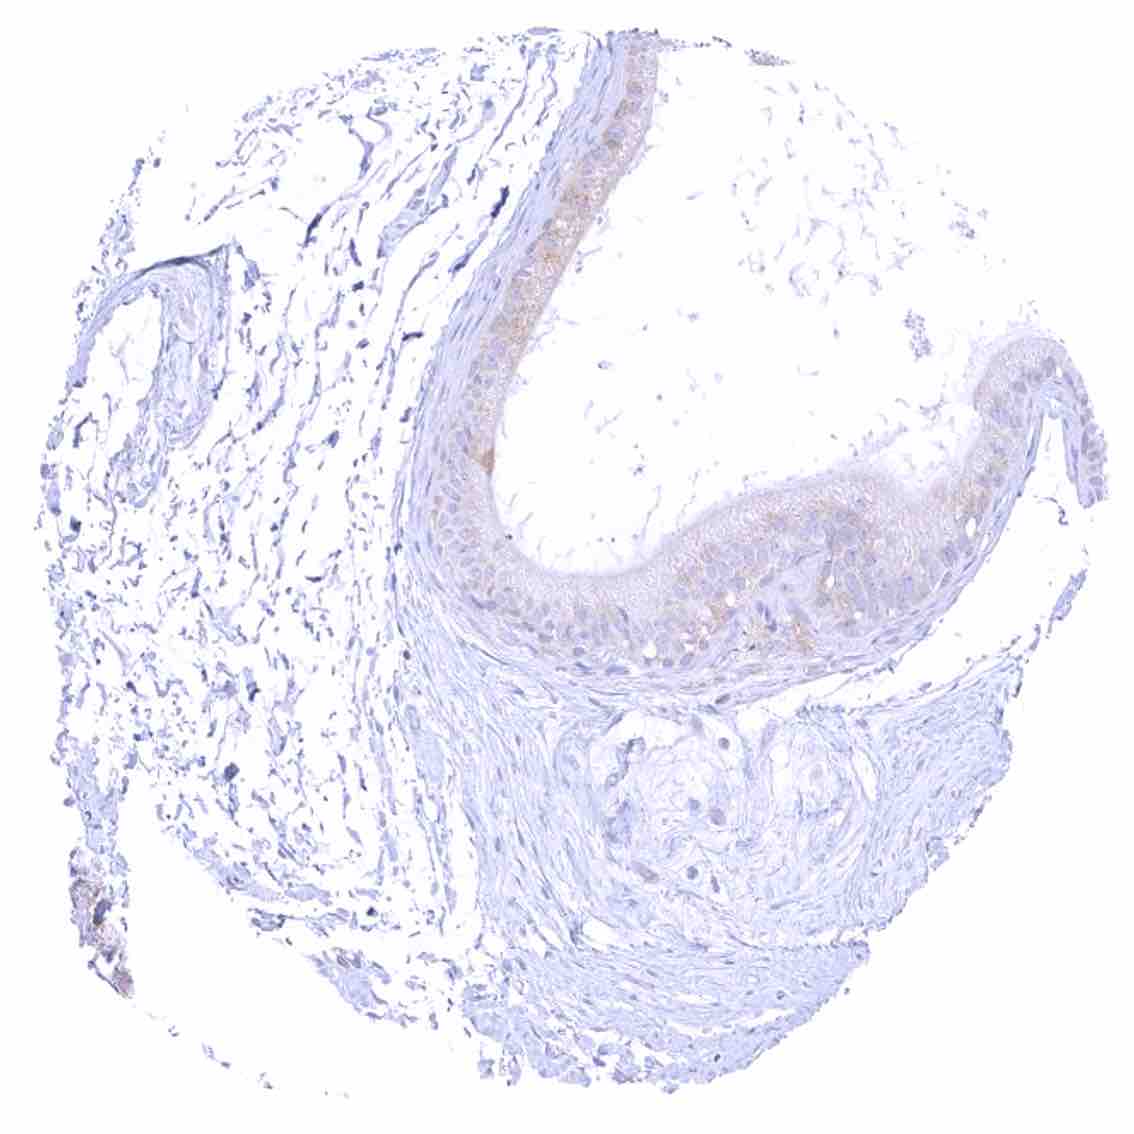

Uterus, endocervix